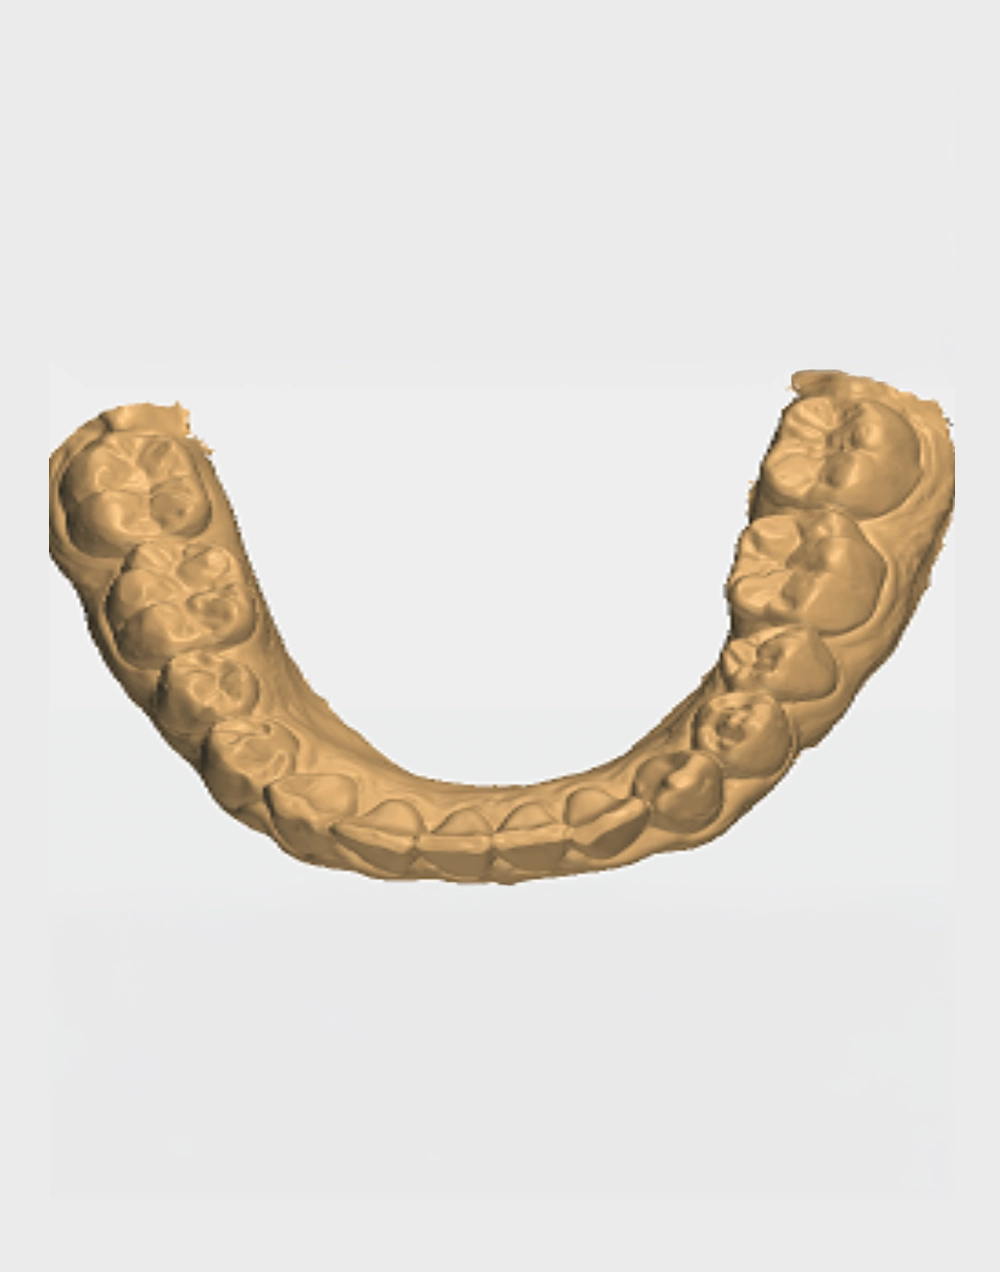

Modelos de

Estudio en Yeso

Escaneo y Modelos Virtuales 3D

La impresión dental 3D se ha convertido en una herramienta valiosa en la odontología moderna, gracias a sus múltiples Beneficios:

• Nos permite observar imperfecciones y malposición de dientes.

• Ortodoncia: Precisión y predictibilidad es lo que hace falta en los tratamientos de ortodoncia para fabricar unos alineadores perfectos.

• Implantología: La cirugía guiada nos permite colocar implantes dentales incluso en los casos más complejos con resultados asombrosos.

• Es rápido, cómodo para los pacientes, incluso los niños lo aceptan mejor, ya que no les genera sensación de sofocamiento o nauseas.

• Escaneo Bucal (Archivos STL)

• Modelos Impresión 3D